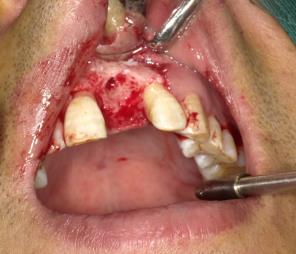

诊断:1、21牙缺失;2、慢性牙周炎 治疗计划 1、 诊治牙周黏膜疾病,行全口牙洁治。 2、 21牙行种植修复(考虑GBR技术) 处置: 21牙种植体植入术+GBR 患者入手术室,取仰卧位,术区行利多卡因+布比卡因阻滞麻醉,碧兰麻于21牙区行浸润麻醉。常规消毒铺单,待麻药显效后,于21牙槽嵴顶做近远中切口,剥离术区黏骨膜,11远中以及22远中做唇侧附加切口。显露术野,见22牙槽窝尚未完全骨充填,唇侧骨量不足。以刮匙刮除局部肉芽组织后,生理盐水冲洗冷却下1.4mm直径球钻确定种植位点,先锋钻确定种植体植入方向。3.5-4.3mm扩孔钻逐级扩大种植窝洞,收集钻头内残留的自体骨备用。用4.3mm攻丝钻在骨壁上攻丝,再用扭矩扳手将种植体旋入。旋上覆盖螺丝,种植体唇侧颈部可见骨缺损区,在骨缺损区周围用小球钻制备多个营养孔。并在唇侧黏膜瓣底部做减张切口,切断黏骨膜,制备复合瓣。收集术区血液,将自体血与骨替代材料混合覆盖于骨缺损区。修剪生物屏障膜至合适的大小和形状,将屏障膜覆盖于骨替代材料上,用自体血液湿润屏障膜至良好贴附状态。无张力关闭牙槽嵴顶切口以及附加切口。常规止血,术毕。 6个月后行种植修复,安置修复基台,戴入修复体后可见龈乳头未安全再生。